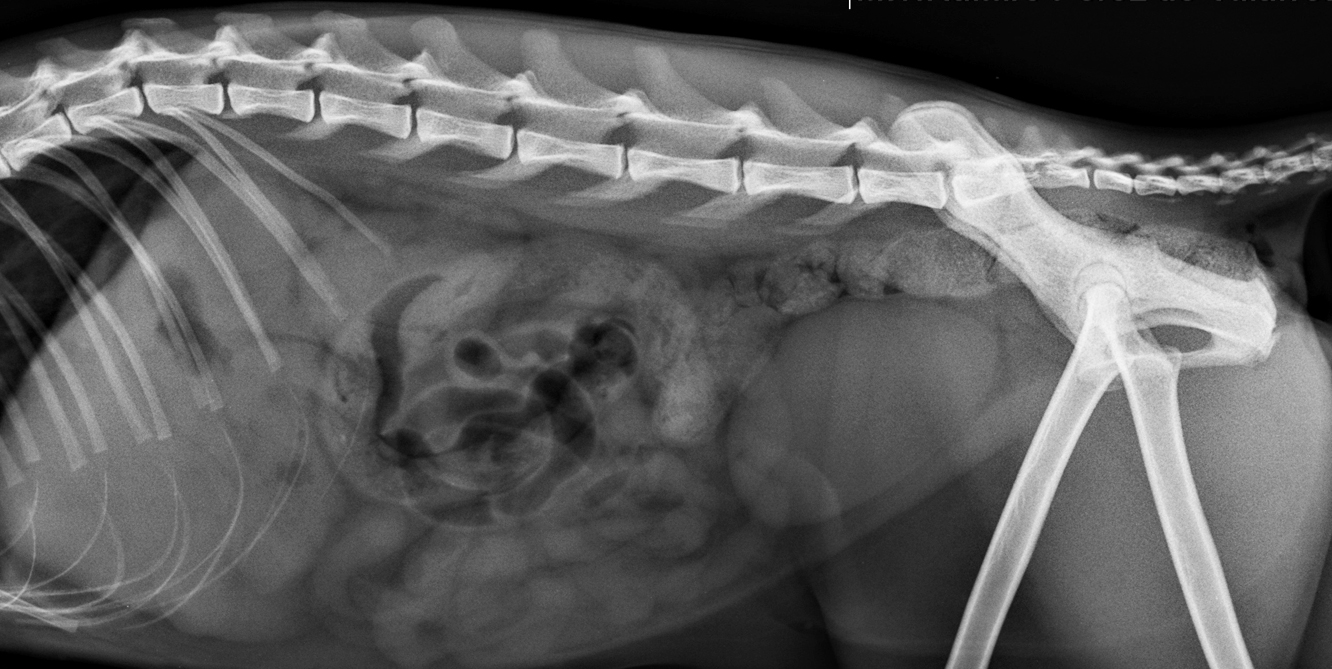

Fidel es un felino macho de 12 años, siamés con dificultades para orinar. Se le realiza ecografía observándose litiasis renal y litiasis vesical (de un lito que migro por el uréter hasta la vejiga. Se realizan radiografías para observación completa de litiasis ureteral y vesical.